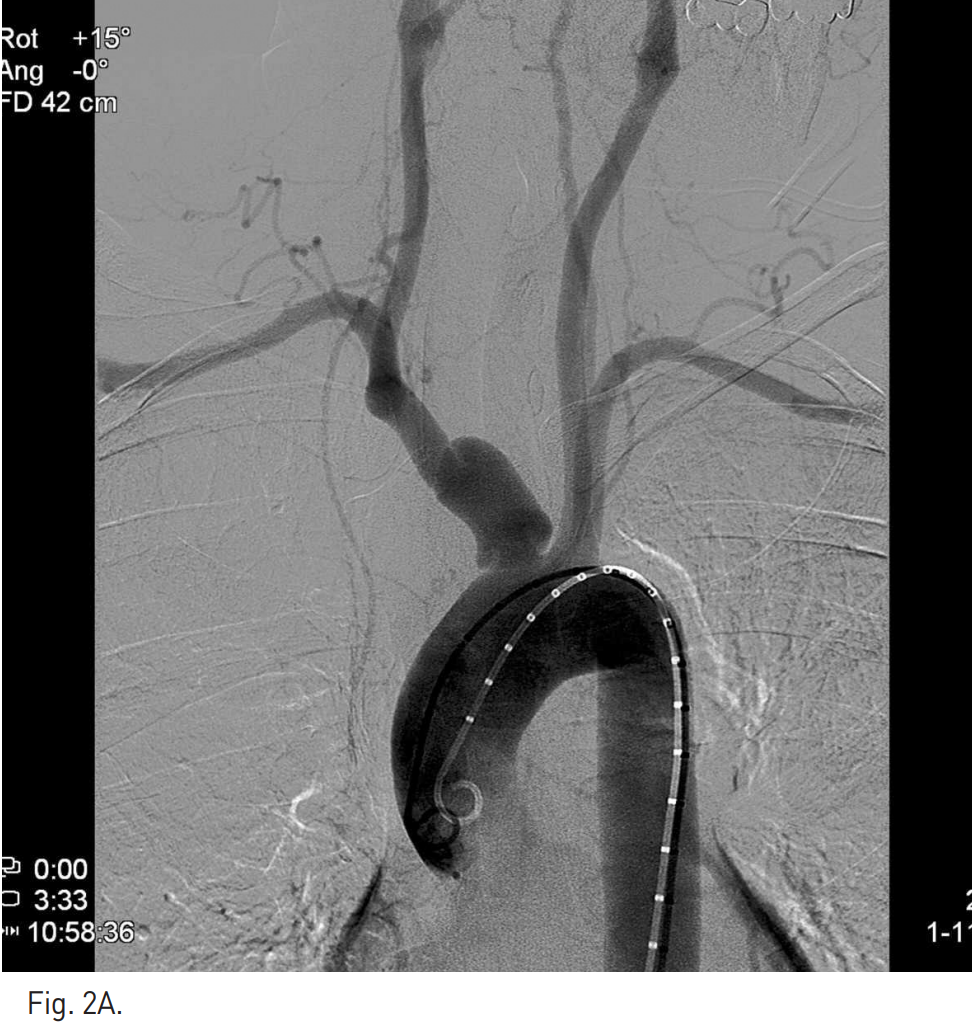

Fig. 2

A. Initial arch aortogram demonstrates the dissection with pseudoaneurysm at the proximal right brachiocephalic trunk.